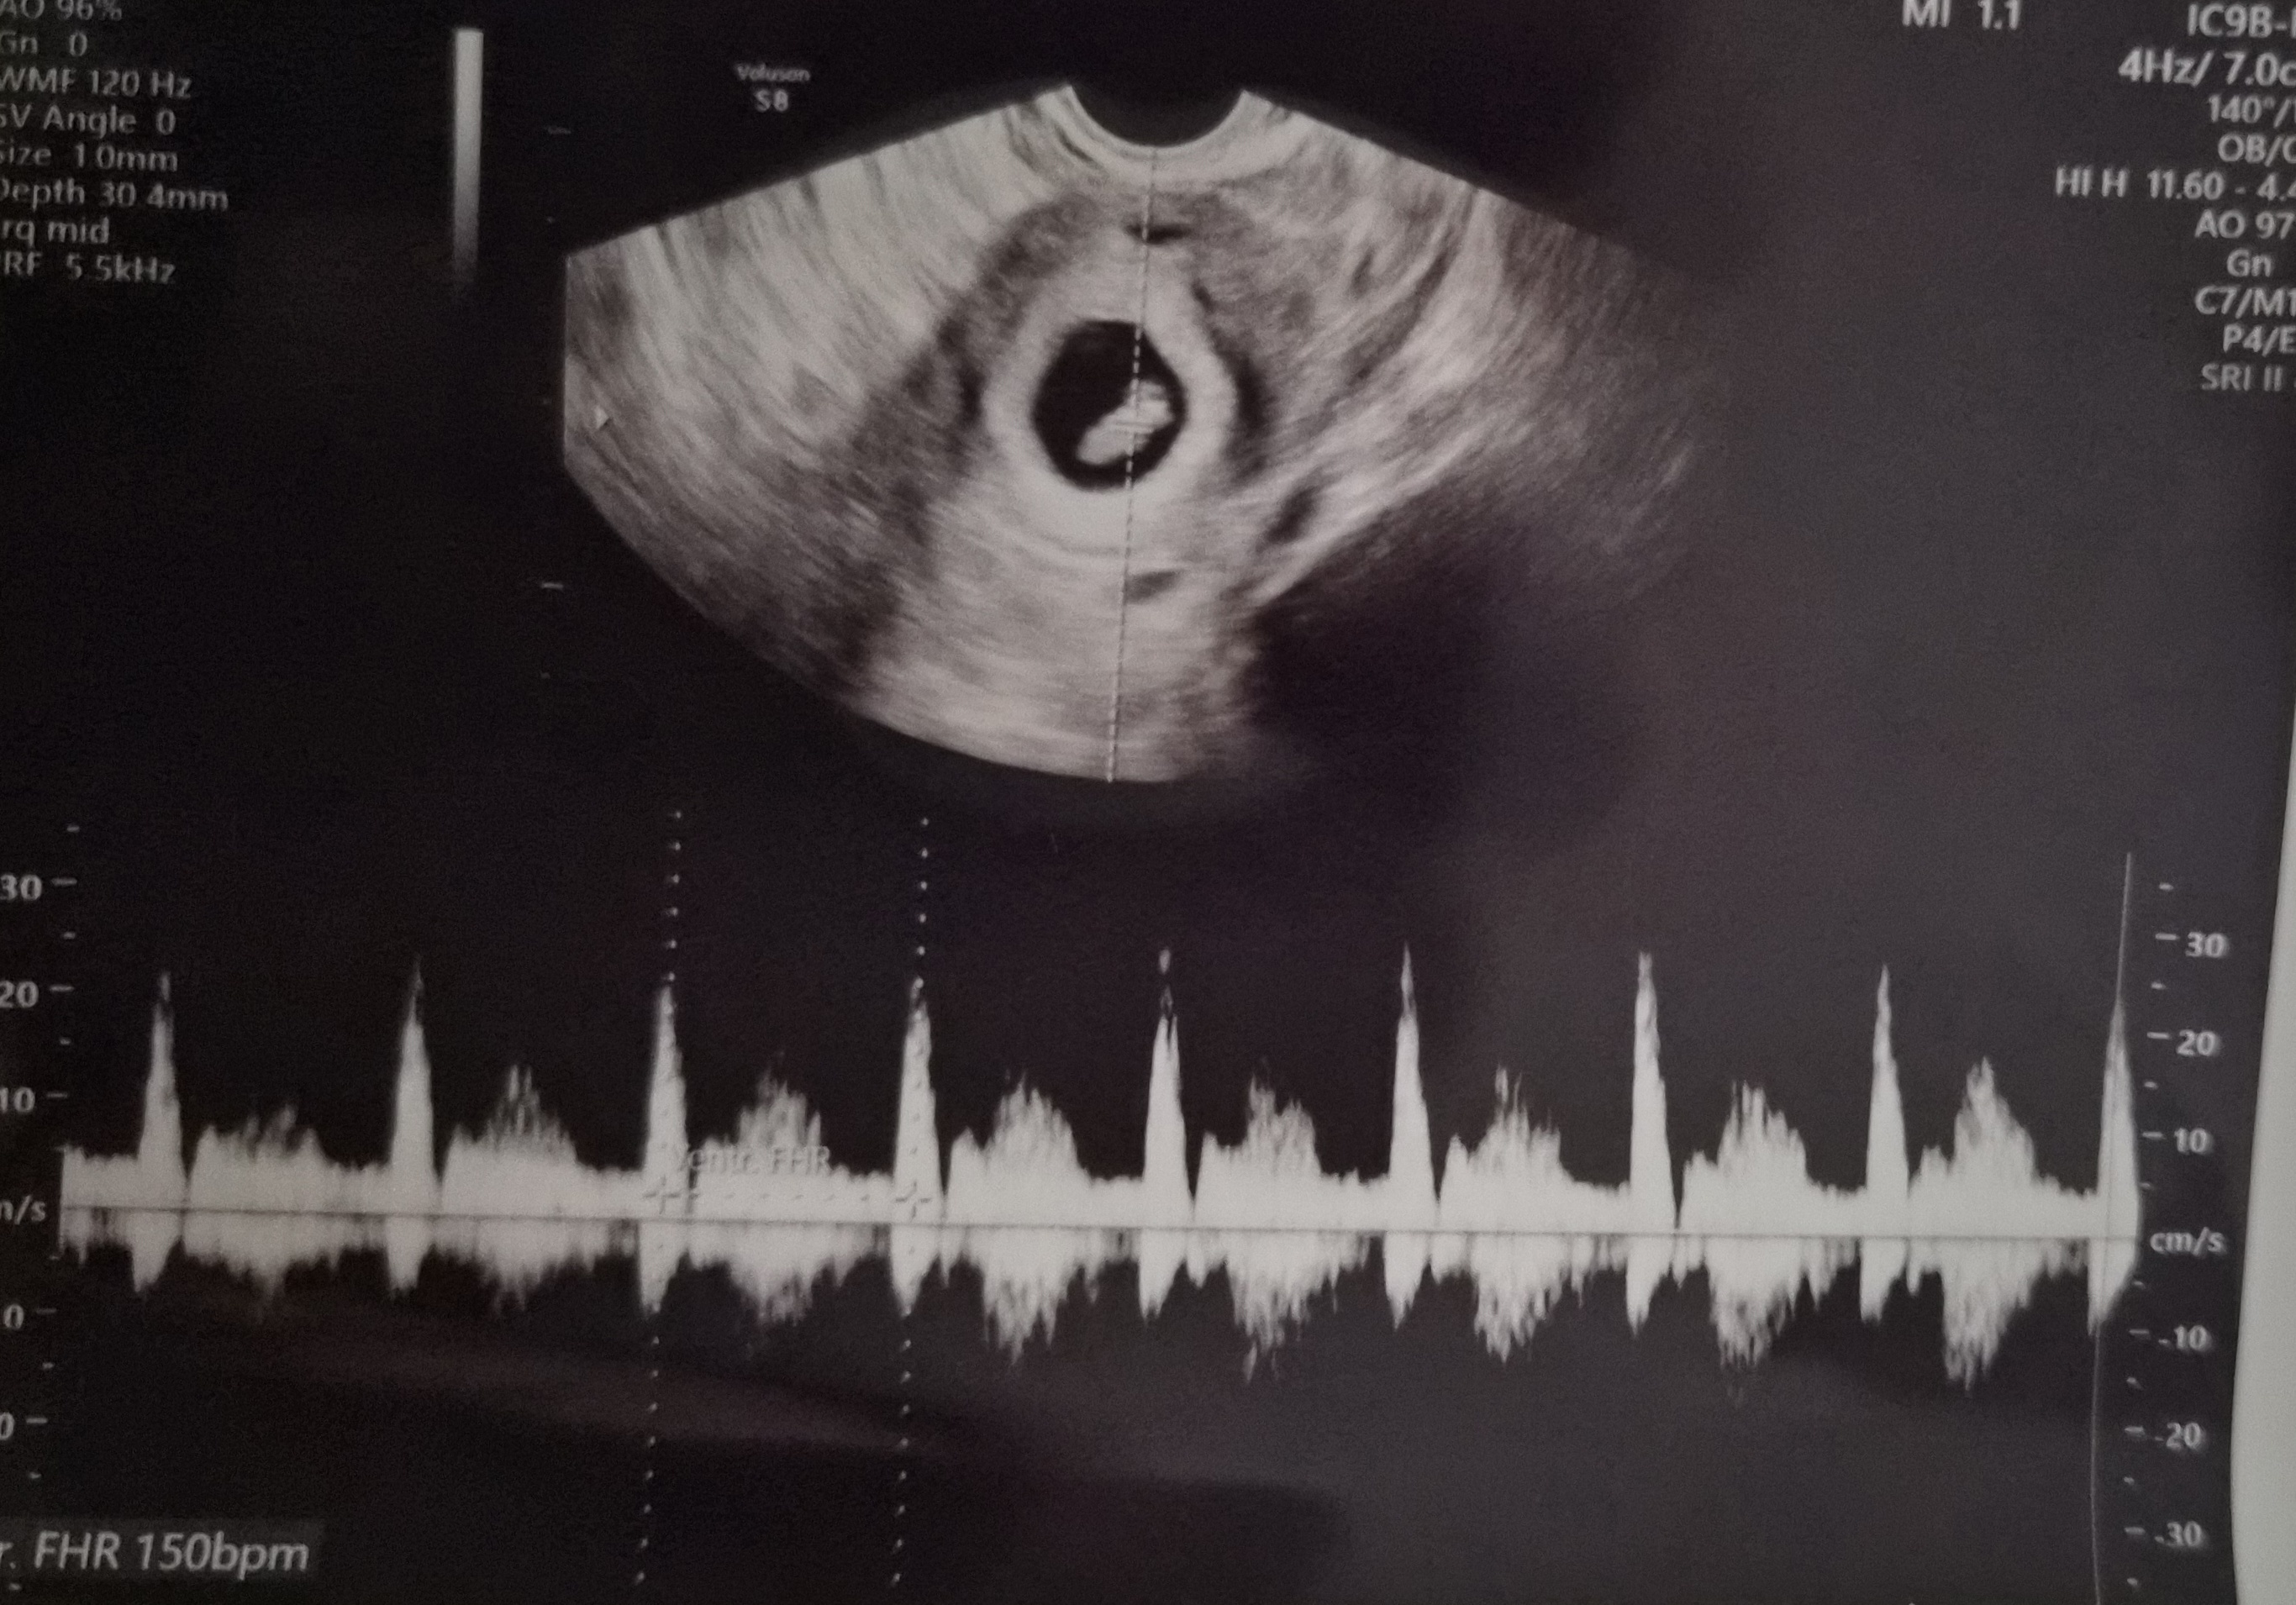

| 치료 도중 느꼈던 가장 기뻤던 순간과 절망적인 것들은 무엇인가요? 잊지 못할 경험이 있나요? | 가장 기뻤던 순간은 이식 후 처음으로 아기집을 확인하고, 이어서 건강한 심장소리를 들었을 때예요. |